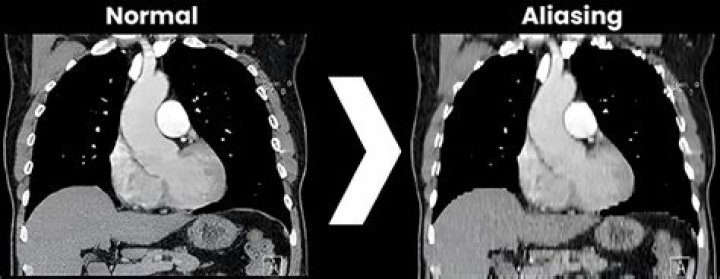

What is aliasing in CT?

Aliasing artifact, otherwise known as undersampling, in CT refers to an error in the accuracy proponent of analog to digital converter (ADC) during image digitization. Image digitization has three distinct steps: scanning, sampling, and quantization.

In radiologic imaging, the term artifact is used to describe any part of an image that does not accurately represent the anatomic structures present within the subject being evaluated.

What is meant by aliasing artifact?